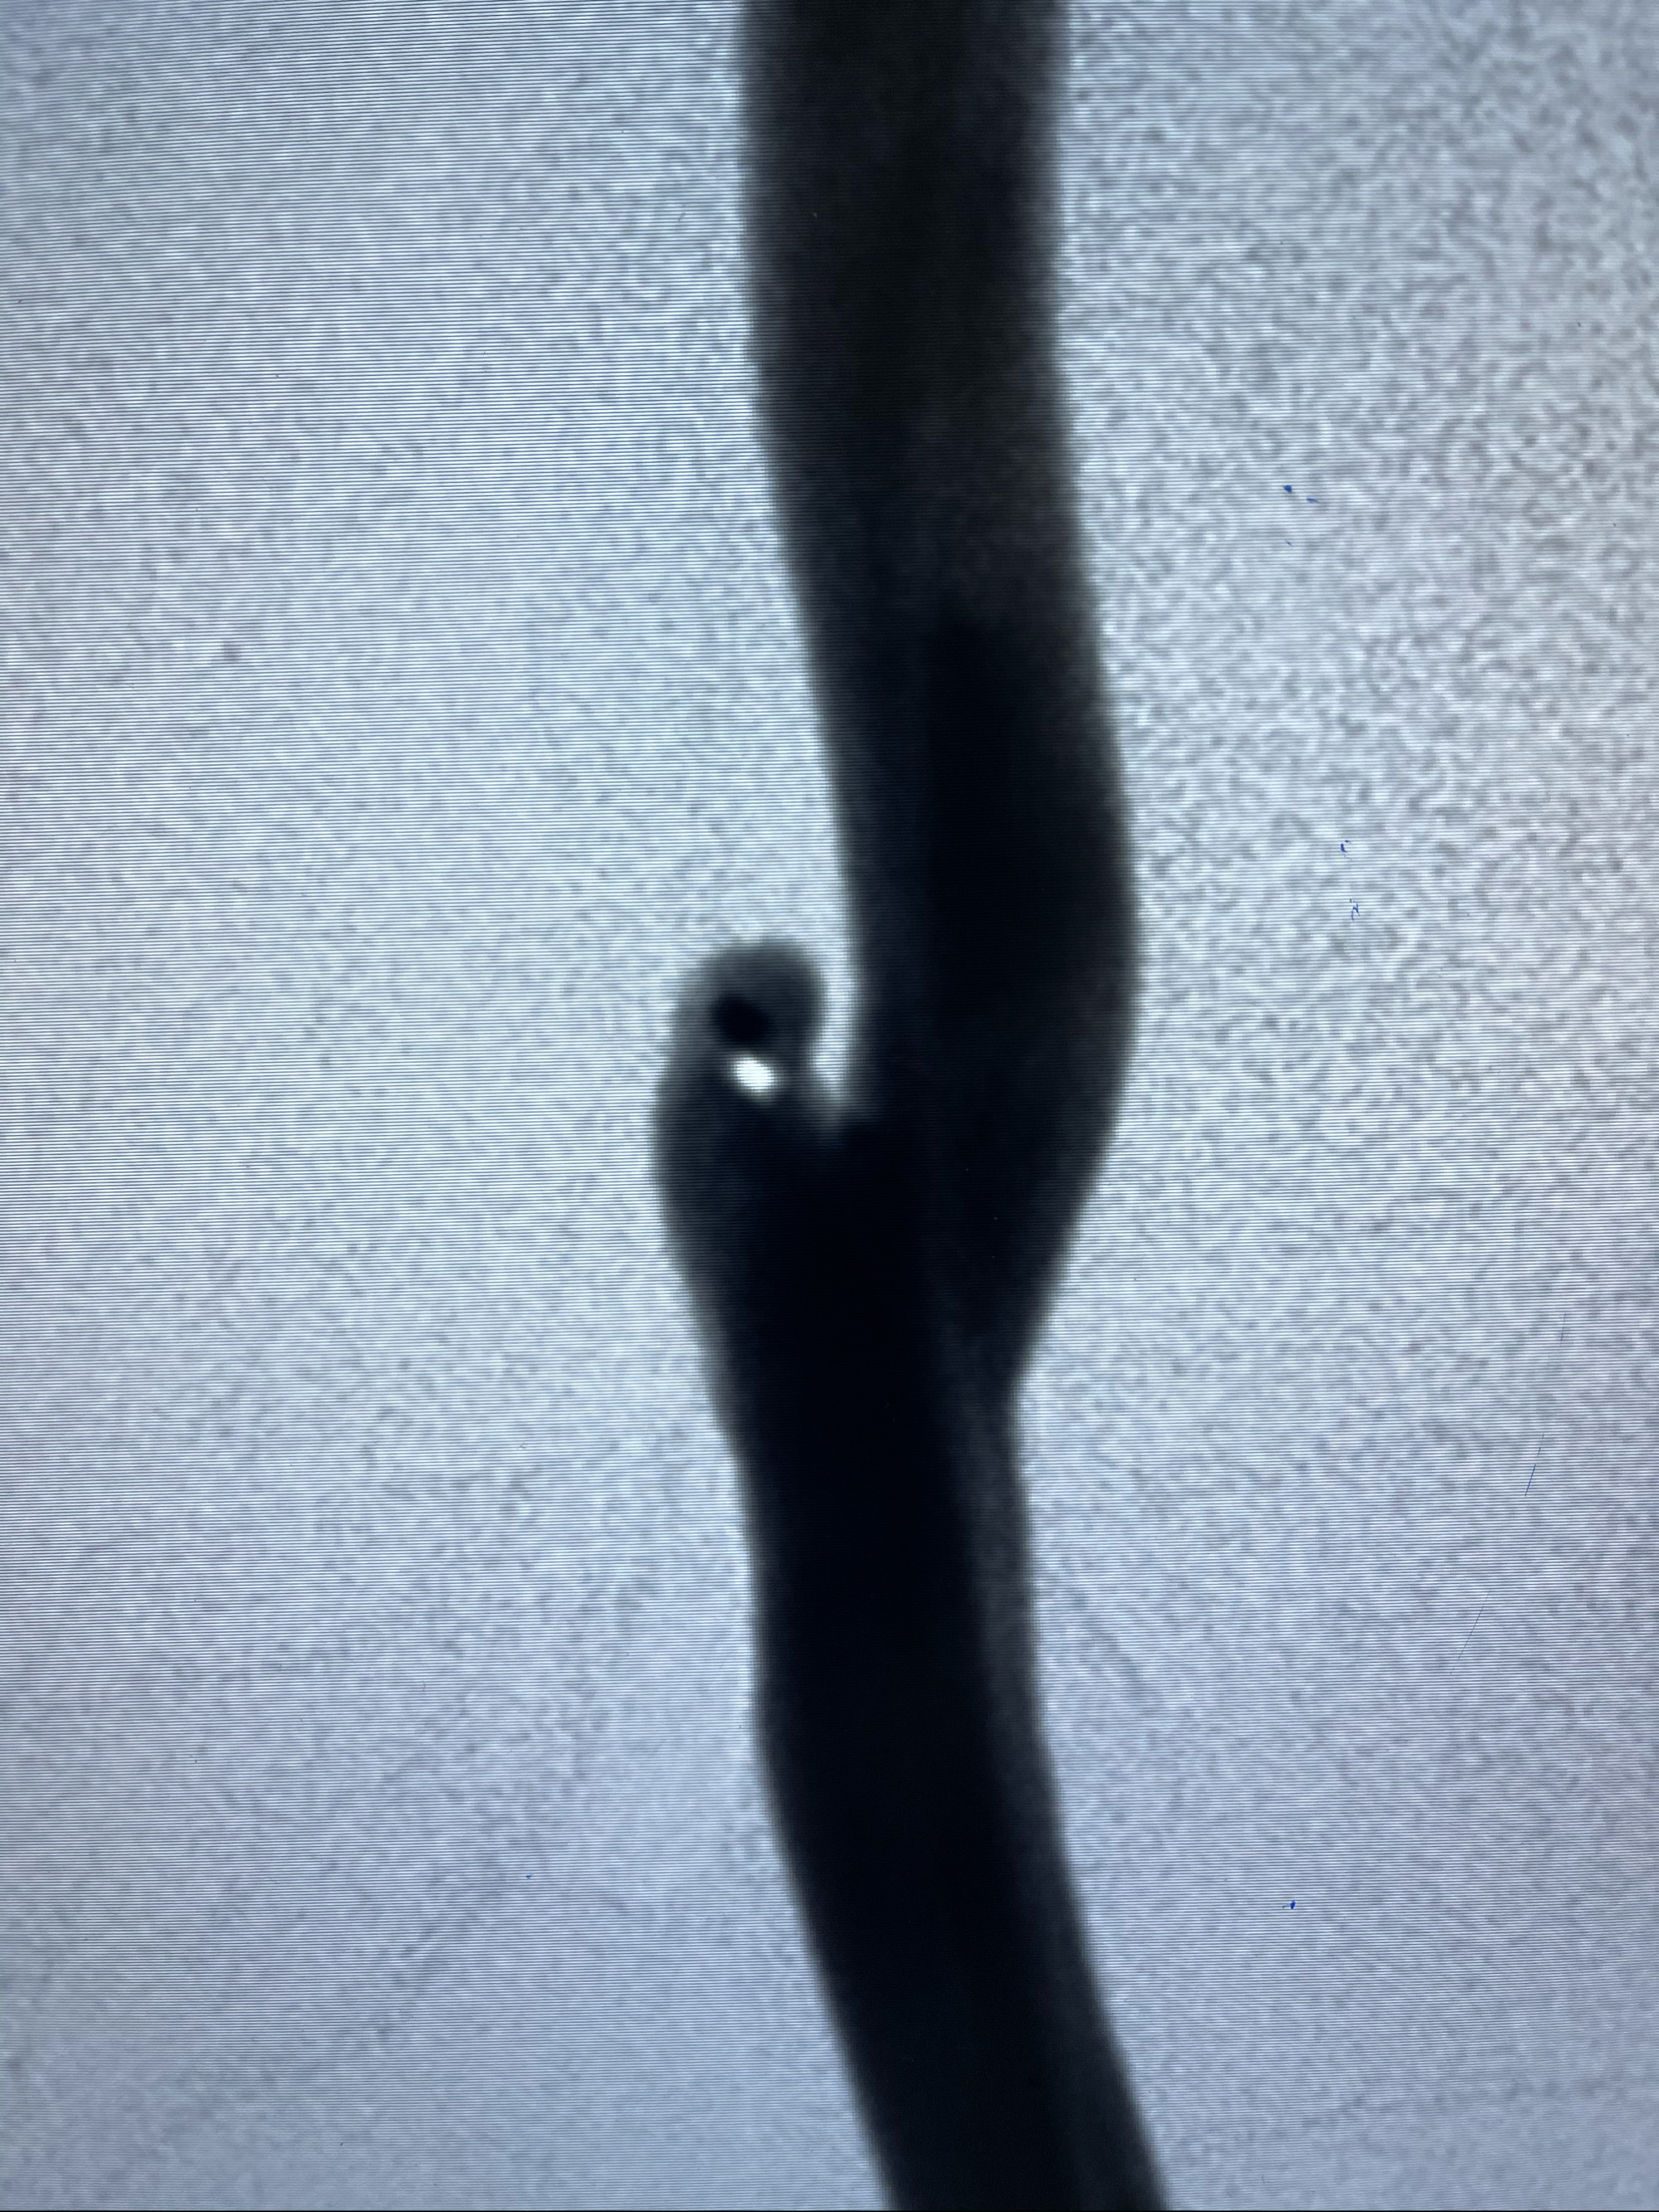

工作角度造影

即刻造影

支架到位